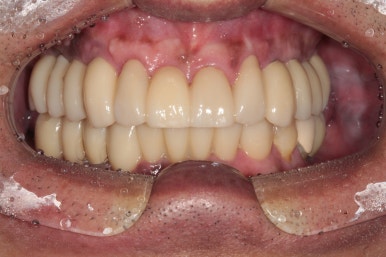

전체 임플란트 완성!!

어느 정도 적응이 되시면, 그 교합을 반영하여 최종 임플란트 크라운을 제작하게 되고 위와 같이 깔끔하게 완성되게 됩니다...

정면부터 비교도 안되게 좋아지신 것을 보실 수 있을겁니다.

위 앞니는 지르코니아 크라운으로, 아래 앞니는 지르코니아 브릿지로 새로 제작하여 적절한 overjet과 overbite를 형성하였고 상당히 자연스러운 외형을 갖춘 것을 보실 수 있을거에요.

또한 앞니를 크라운으로 제작하면서 치아의 색상도 보다 톤업해드렸고, 치아 배열도 가지런하게 그리고 치아 사이 공간도 모두 닫아드려 정말 한결 젊어졌다는 느낌이 듭니다.

임플란트를 엄청 많이 심지 않았지만, 적절한 개수를 식립해냄으로써 성인 남성도 식사가 가능할 정도의 임플란트 크라운을 제작해드릴 수 있었습니다.

앞니와 어금니를 한 번에 다 같이 만들었던 만큼, 크라운 색상의 조화가 기가막혀 진짜 내 이같아 보이네요..!!

이렇게 가지런한 치열은 바로 자신감을 가져다 주기도 합니다.